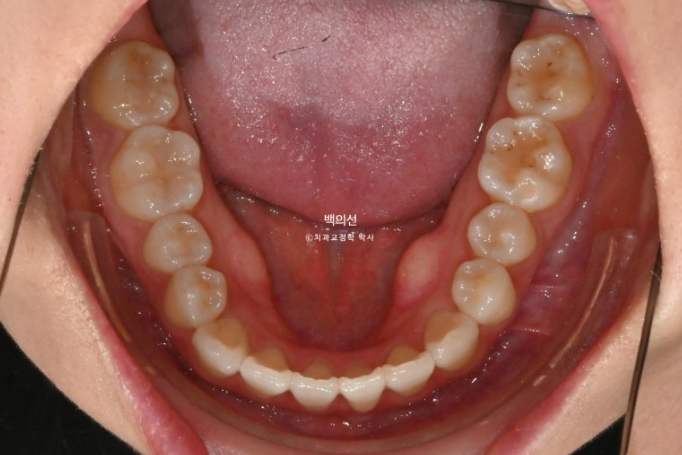

오래 전 했던 교정으로 어금니 교합은 나쁘지 않은 상태입니다.

인비절라인 라이트로 앞니 배열과 뿌리를 뼛속으로 깊이 넣어주는 치료를 권유드렸습니다.

교합은 좋습니다.